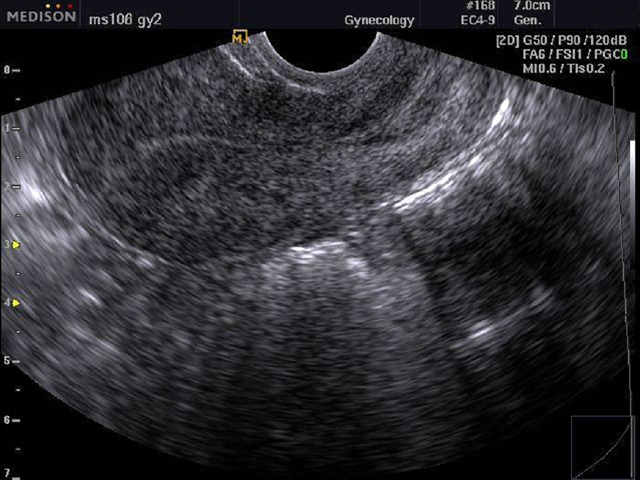

Трансвагинальная УЗИ-диагностика

Размеры матки в норме у женщин, расположение органа, толщину эндометрия и расположение яичников позволяет наиболее точно выявить трансвагинальная диагностика. Для этого датчик, который представляет собой пластиковый стержень 12 см в длину, вводится на небольшую глубину.

Процесс не доставляет неудобств, так как используется специальный гель, а диаметр устройства составляет всего 3 см. Из-за небольшой толщины стенок влагалища удается обнаружить любые, даже незначительные изменения. Благодаря этому, удается установить точный диагноз и подобрать своевременное лечение.

Узнать, в норме ли размеры матки у женщин можно благодаря трансвагинальному УЗИ.